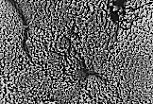

L'aspect mamelonné de la surface des replis d'un estomac de rat (région fundique) est ici observé au M.E.B..

Toute cette surface est perforée d'orifices correspondant à l'abouchement des cryptes.